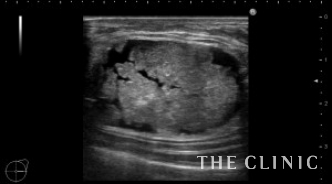

この方は3年前に他院で脂肪注入による豊胸をされました。

両側に充実性の大きなしこりを認めました。被膜も厚そうです。